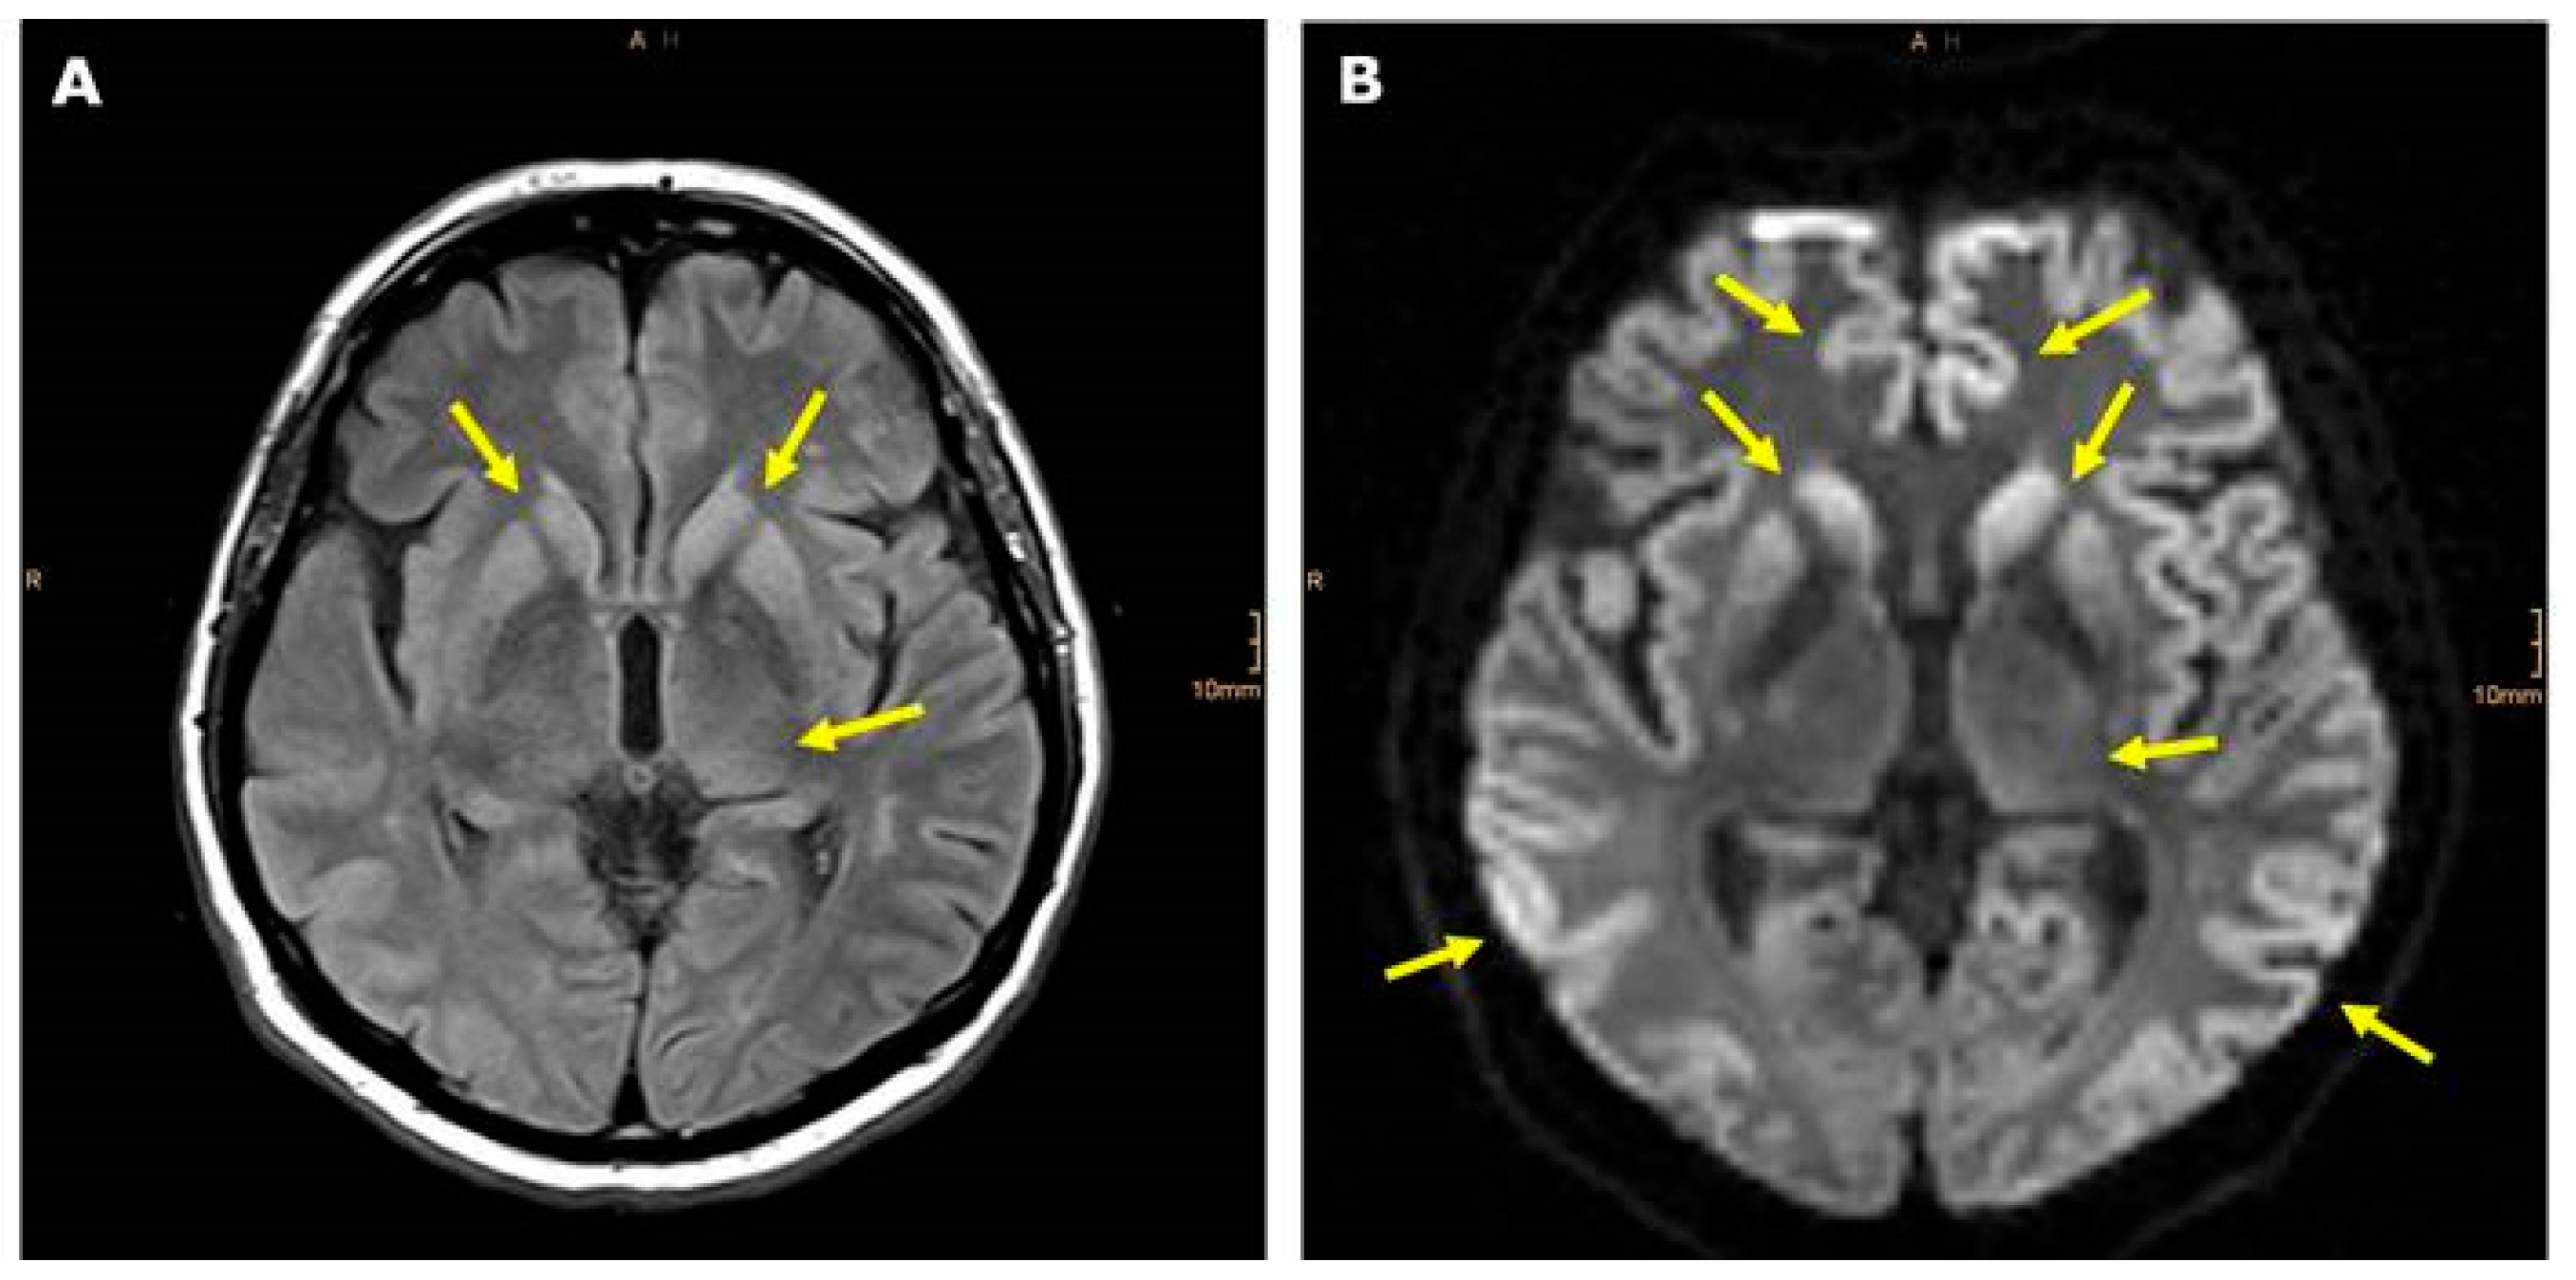

Imaging of CreutzfeldtJakob Disease Imaging Patterns and Their Creutzfeldt Jakob Disease Diagnosis It belongs to a group of human and animal diseases known as. Several forms of the disease have been described,. A brain biopsy or an exam of brain tissue after death, known as an autopsy, is the gold standard to confirm the. There are standard diagnostic criteria for definite, probable and possible sporadic cjd cases. A brain biopsy is the.. Creutzfeldt Jakob Disease Diagnosis.

Imaging of CreutzfeldtJakob Disease Imaging Patterns and Their Creutzfeldt Jakob Disease Diagnosis There are separate diagnostic criteria for cases that may be iatrogenic and those. It belongs to a group of human and animal diseases known as. A brain biopsy or an exam of brain tissue after death, known as an autopsy, is the gold standard to confirm the. A brain biopsy is the. Several forms of the disease have been described,.. Creutzfeldt Jakob Disease Diagnosis.

Imaging of CreutzfeldtJakob Disease Imaging Patterns and Their Creutzfeldt Jakob Disease Diagnosis It belongs to a group of human and animal diseases known as. There are separate diagnostic criteria for cases that may be iatrogenic and those. A brain biopsy is the. A brain biopsy or an exam of brain tissue after death, known as an autopsy, is the gold standard to confirm the. Several forms of the disease have been described,.. Creutzfeldt Jakob Disease Diagnosis.

Imaging of CreutzfeldtJakob Disease Imaging Patterns and Their Creutzfeldt Jakob Disease Diagnosis There are standard diagnostic criteria for definite, probable and possible sporadic cjd cases. A brain biopsy or an exam of brain tissue after death, known as an autopsy, is the gold standard to confirm the. It belongs to a group of human and animal diseases known as. Several forms of the disease have been described,. There are separate diagnostic criteria. Creutzfeldt Jakob Disease Diagnosis.

Imaging of CreutzfeldtJakob Disease Imaging Patterns and Their Creutzfeldt Jakob Disease Diagnosis There are standard diagnostic criteria for definite, probable and possible sporadic cjd cases. A brain biopsy is the. Several forms of the disease have been described,. It belongs to a group of human and animal diseases known as. There are separate diagnostic criteria for cases that may be iatrogenic and those. A brain biopsy or an exam of brain tissue. Creutzfeldt Jakob Disease Diagnosis.